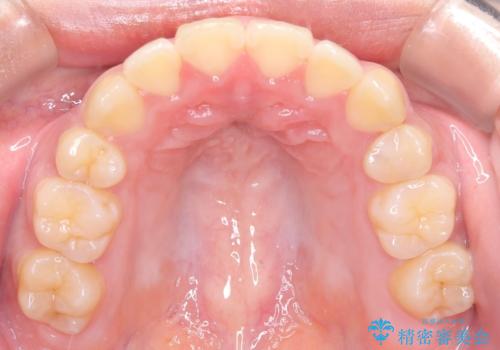

- 八重歯と口元が出ていることを主訴に来院されました。

レントゲンの検査において、前歯も外側に傾いてる結果であったため、上下左右の小臼歯を抜歯して配列を行いました。

歯の動きも良く短期間で治療を終えられたため患者さんにも大変満足していただきました。